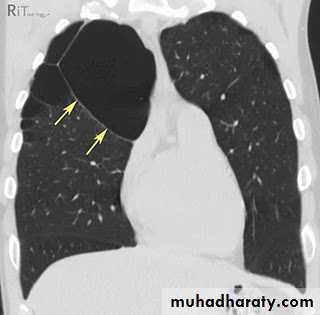

Bronchectasis

Abnormal irreversible dilatation of bronchioles with thickening of their walls . Presented with recurrent pneumonias & haemoptysis ..Types:Cystic

Fusiform

Cylendrical

In which the bronchiole is wider than the near by vascular branch

Causes –infancy & childhood infection

-TB

-pulmonary fibrosis

-cystic fibrosis

-immotile cilia syndromes